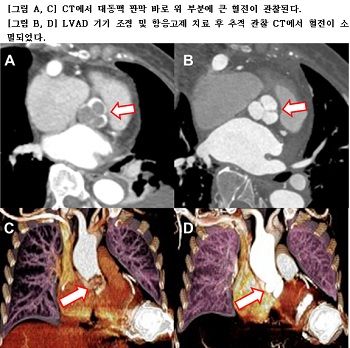

LVAD 펌프 속도를 조절하여 혈전으로 인한 전신 색전증이나 심근경색이 발생하지 않도록 한 결과, 3주 후 혈전은 사라지고 환자는 특별한 부작용이나 합병증 없이 호전되어 퇴원했고, 심부전 증상 없이 일상생활이 가능해졌다.